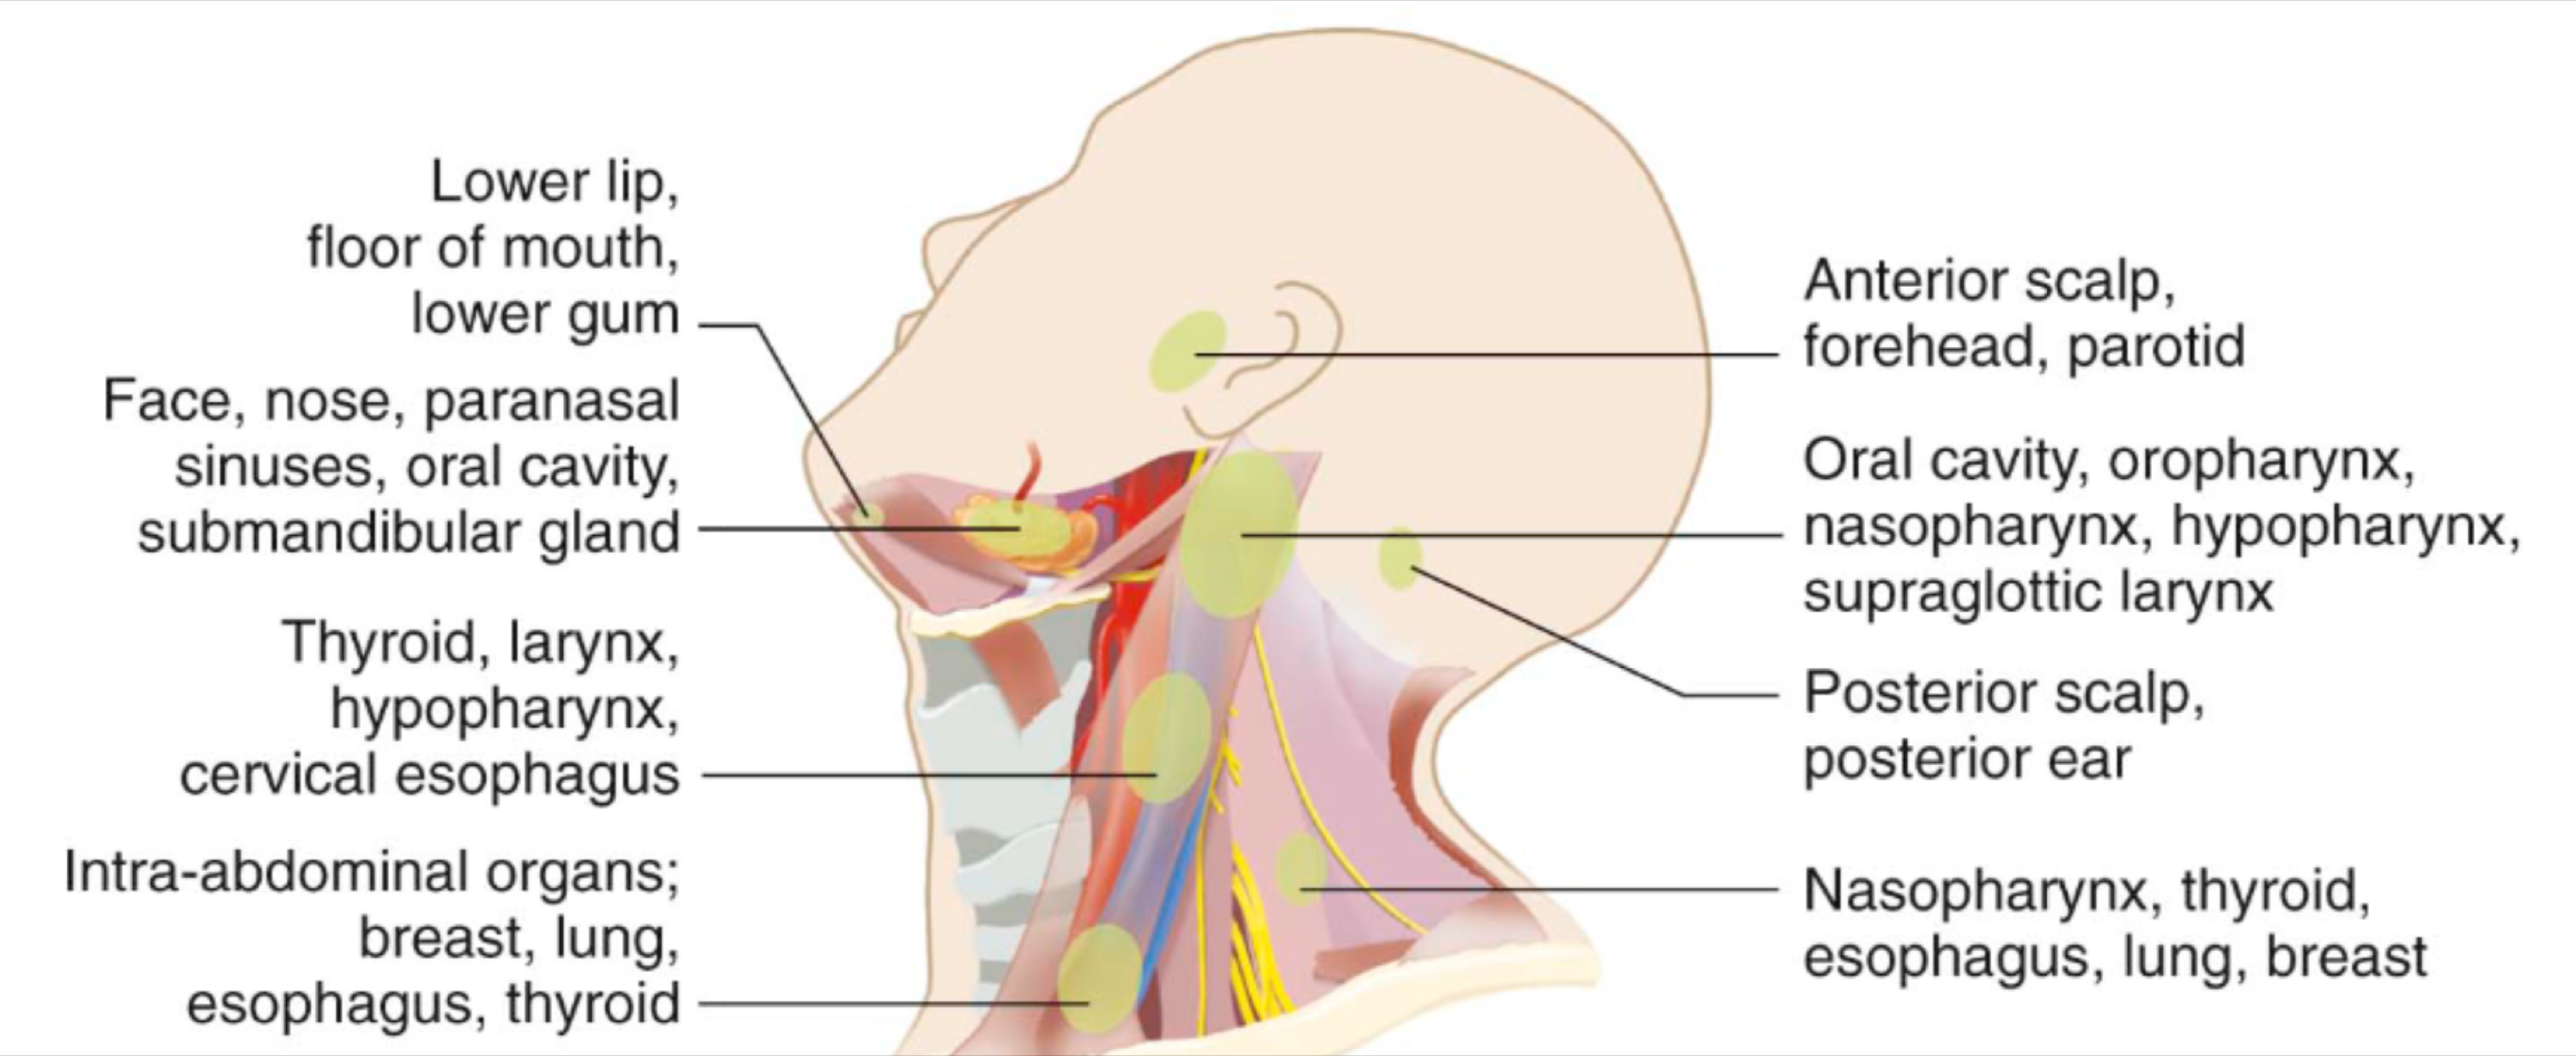

Lymphatic system

總圖

Nodes

Groups

- Level I

- the submental group (Ia), and the

submandibular group (Ib). - Level II

- the upper jugular lymph nodes

- level IIa – CN XI 前

- level IIb – CN XI 後

- Level III

- the middle jugular lymph nodes

- Level IV

- the lower jugular lymph nodes

- Level V

- all lymph nodes contained within the posterior triangle

- Level VI

- lymph nodes of the anterior (central) neck compartment

Tip

清除 I, II, III

Nasal cavity

Oral cavity

Tongue

Tonsil

Waldeyer’s tonsillar ring

Face

- Maxillary

- Buccinator

- Supramadibular

Larynx

用vocal fold 分,上,下分別到SDC, IDC

Thyroid

跟著Sup./ Inf. thyroid a.走,分別到SDC, IDC

Nose